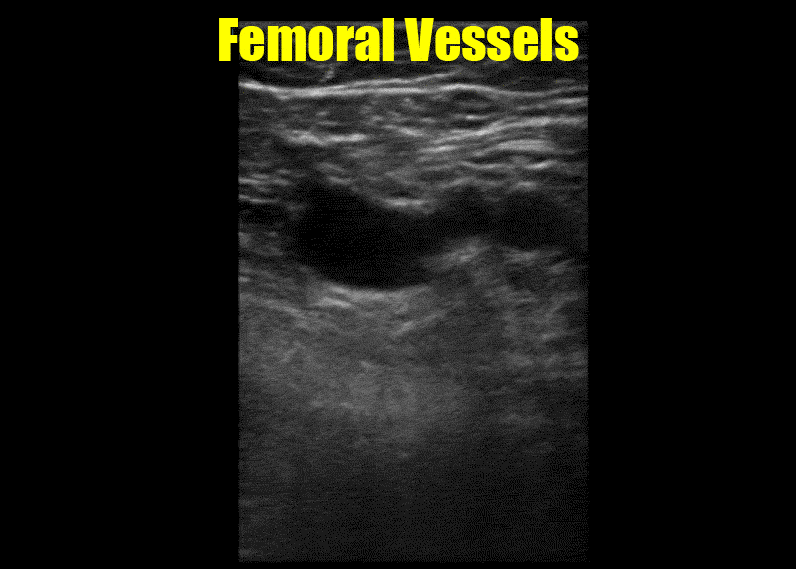

To master the other issues, an understanding of the anatomy is crucial. The image below shows the relationships among the vessels and highlights where the imaging zones are.